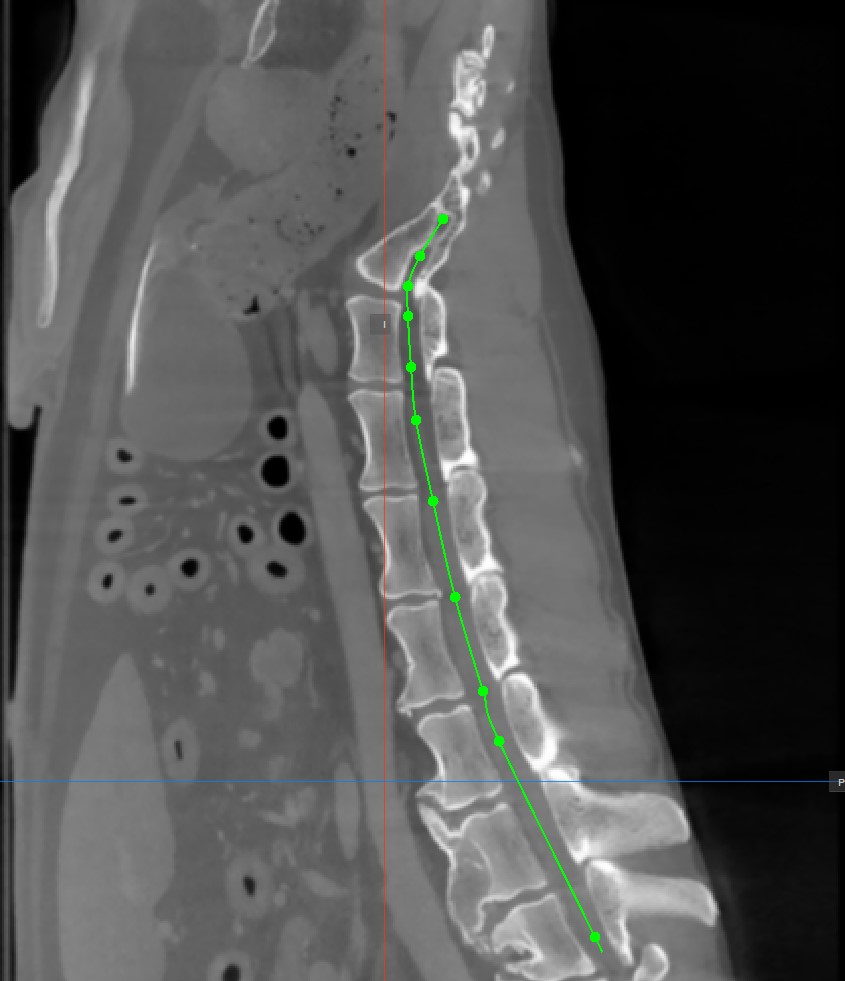

Curved MPR (CMPR) View

Curved MPR, a variation of MPR, creates cross-sectional images along a user-drawn curved path. CMPR can be especially useful when visualizing complex or irregular structures, such as blood vessels or various spinal structures.

The Curved MPR requires a user-drawn path in order to generate the cross-sectional images. Select the Add CMPR Point tool located at the bottom section of the CMPR view to draw the required path.

• The points generating the path have to be placed on one of the three available standard MPR viewports on the right side of the window. Choose the most appropriate plane for the requirements.

• At least two points have to be placed on the images in order to generate the path. The CMPR view will be more detailed when more points are used to draw the path.

• To complete the path, toggle the Add CMPR Point tool again, or double-click with the mouse on the image after placing the last point of the path. The path will be marked in green once it’s finalized.